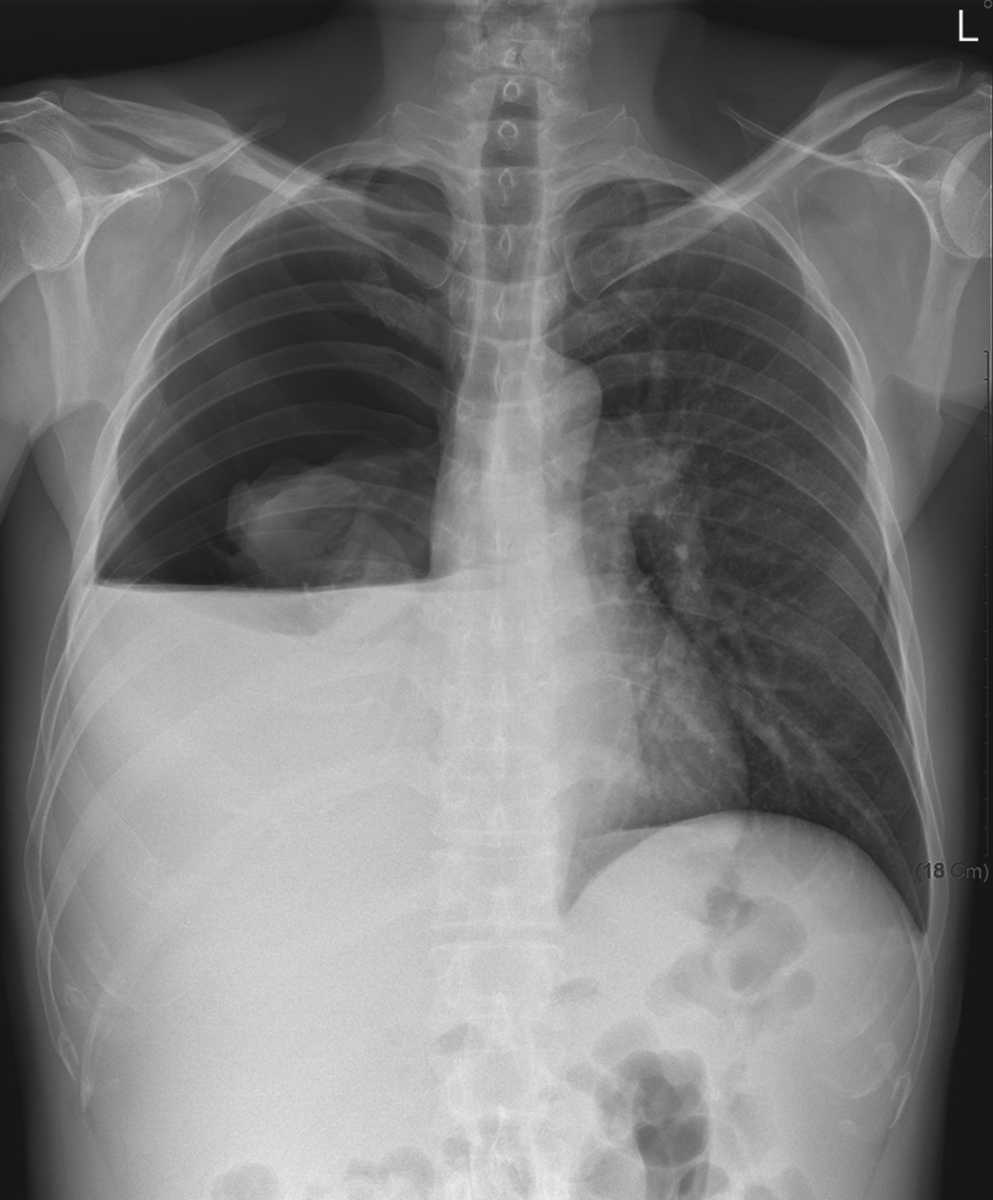

A 47-year-old man with a history of cirrhosis associated with alcohol abuse presented with a 2-day history of shortness of breath. What’s the likely diagnosis/radiologic finding? @ManualOMedicine #MedEd

BrownJHM's tweet image. A 47-year-old man with a history of cirrhosis associated with alcohol abuse presented with a 2-day history of shortness of breath. What’s the likely diagnosis/radiologic finding? @ManualOMedicine #MedEd